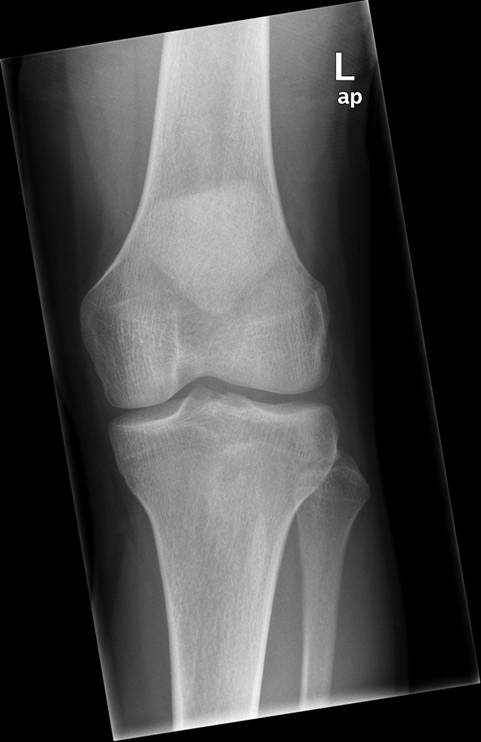

Knæ, Normal, Røntgen

Normalt røntgenbillede af venstre knæ i 2 projektioner.